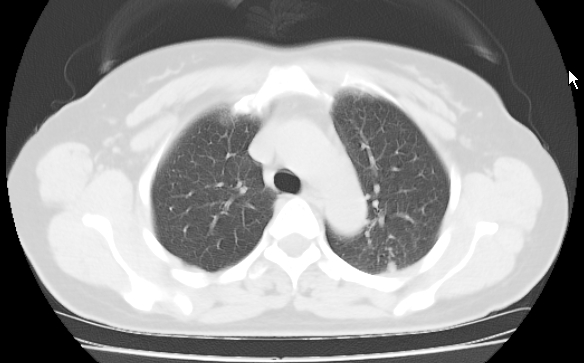

标题: CT25227:背部疼痛伴双侧胸壁痛2月,食欲差。 [打印本页]

标题: CT25227:背部疼痛伴双侧胸壁痛2月,食欲差。

肺结核并胸椎结核?请各位高手指教。

考虑胸椎结核并椎旁软组织肿胀。

考虑胸椎结核并椎旁软组织肿胀。 支持